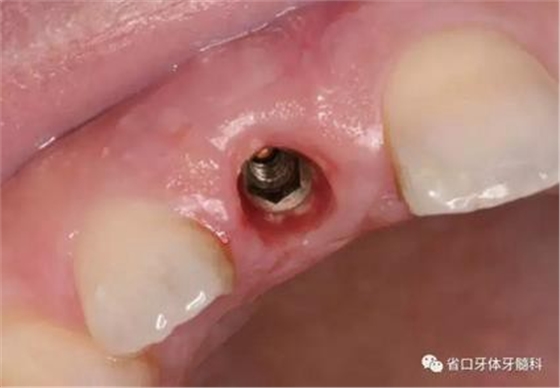

(3)術(shù)后醫(yī)囑與牙齦塑形:術(shù)后予以抗炎止痛對癥處理,7~10天拆 線。術(shù)后3個月開始逐步調(diào)整臨時冠并塑形牙齦形態(tài),控制上頜右側(cè)中切牙 近遠(yuǎn)中牙齦乳頭的充盈量和齦緣水平,使得上頜右側(cè)中切牙牙齦形態(tài)與上頜 左側(cè)中切牙盡量相對稱。

圖25 術(shù)后3個月

圖26 牙齦塑形